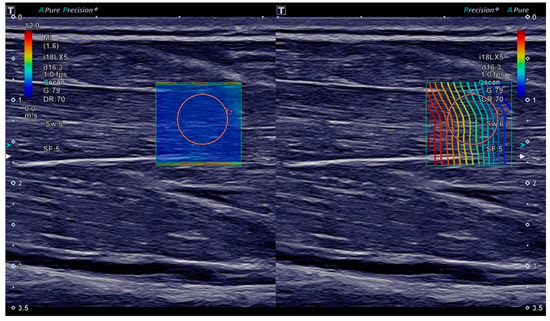

For ultrasound measurements, the participants were sitting, with their elbow flexed approximately 90 degrees and their forearm supinated and placed on the thigh. We always examined the right arm. The ultrasound transducer was held by hand and positioned so as to obtain a longitudinal B-mode view of the flexor digitorum superficialis muscle in the middle third of the forearm, parallel to the muscle fibres. We targeted the flexor digitorum superficialis muscle because hand-grip is classically affected in myotonia and because of the methodical resemblance to the use of hand-grip dynamometers in myotonia. As SWE measurements are known to become more noisy with increasing depth [28,29], we measured the superficial instead of the deep finger flexor muscle. A square ROI in the flexor digitorum superficialis muscle was selected in the B-mode image for continuous shear wave elastography (SWE) with a frame rate of 1/s (Figure 1). Only minimal, constant contact force was applied with the transducer as is generally recommended [14,29].

(1) With participants having been instructed to relax their forearm and hand, SWE imaging was performed for 5 s (time −9 s to −5 s) for baseline measurements. At this stage, SWE quality was assessed visually in the shear wave velocity and propagation maps—if insufficient, the transducer was repositioned and imaging was restarted. Only if a homogeneously low (<2.5 m/s) shear wave velocity was observed in multiple successive images without artifacts (as in Figure 1), the imaging sequence was continued, keeping the transducer position in place.

Figure 1. Ultrasound B-mode and shear wave elastography (SWE) imaging of the flexor digitorum superficialis muscle. On both sides of the screen, the same B-mode image of the muscle in the longitudinal plane is displayed. On the left, a shear wave velocity map is overlaid with the colour scale ranging from 0.0 m/s (blue) to 12.0 m/s (red). On the right, a proprietary shear wave propagation display is shown, meant to depict the shear wave wavefront. The orange circles are the shear wave velocity measurement ROI placed after acquisition.